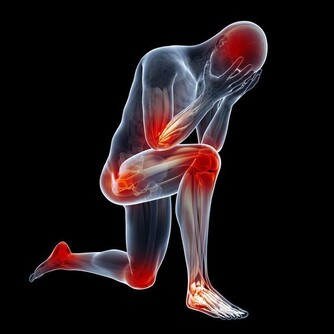

4、疼痛。患有前列腺癌的男性會出現腰部、骶部、臀部、髖部疼痛,骨盆、坐骨神經痛等症狀。

有的時候患者腰部、骶部、臀部、髖部疼痛,骨盆、坐骨神經痛,這時候疼痛是十分劇烈的,能由於癌灶轉移至骨骼或侵犯神經或腎積水、腎感染所致。了解這個症狀是對於前列腺癌晚期的治療是較為重要的。